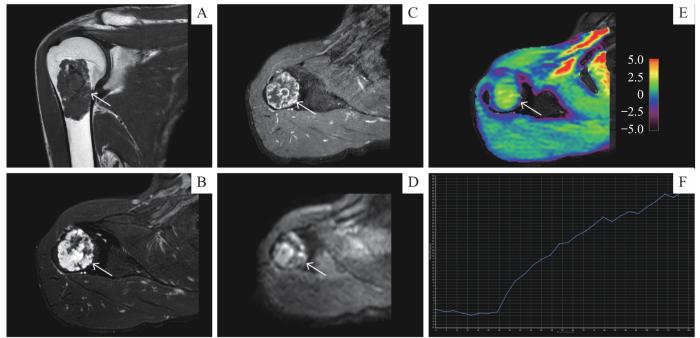

病例1,男,52岁,因体检发现右侧肱骨近端占位收治入院。术前常规MRI增强检查结果( 图4)示右侧肱骨近端可见边界清晰长椭圆形肿块影,肿块最大直径约4.94 cm,T1WI呈低信号,T2WI压脂呈高低混杂信号,增强后呈明显不均匀强化。DCE-TIC为Ⅰ型,DWI呈高信号,ADC值2.16×10 -3 mm 2/s,术前影像诊断考虑良性可能。但APTw成像测得APT值为2.28%,提示该病变恶性可能( 图4E)。术后病理提示右侧肱骨软骨肉瘤Ⅰ级,与APTw成像的恶性提示结果一致。

图4

图4   APTw成像在恶性骨肿瘤中的应用

Note: A 52-year-old male with chondrosarcoma of the right humerus. A. Coronal T1-weighted MRI sequence. B. Axial T2-weighted fat-saturated MRI sequence. C. Axial contrast-enhanced T1-weighted MRI sequence. D. Axial DWI ( b=1 000 s·mm -2) sequence. E. Axial APT image fused with axial T2WI (the color bar indicates the APT values). F. TIC classification (type Ⅰ).

Fig 4   Application of APTw imaging to malignant bone tumor